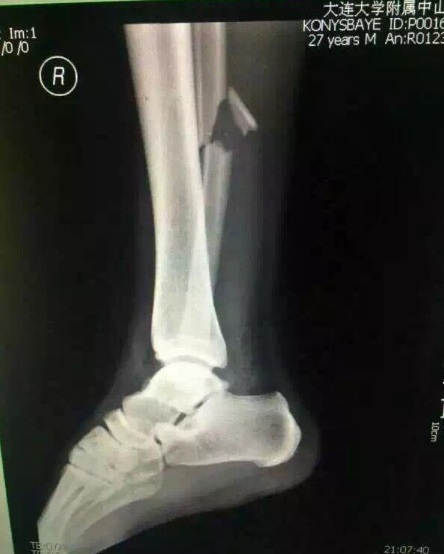

Китайские СМИ опубликовали рентгеновский снимок ноги Конысбаева

Как сообщает Sina.com.cn, в сети появился рентгеновский снимок правой ноги футболиста сборной Казахстана Улана Конысбаева, получившего тяжёлую травму в товарищеском матче с Китаем (1:0), информирует Sports.kz.

Конысбаев боролся за мяч с Жэнем Ханом, после чего неудачно приземлился стопой на газон. Улан на носилках покинул поле, а затем в сопровождении врачей был доставлен в одну из клиник Даляня. Предварительный диагноз — перелом голеностопа. Ожидается, что на полное восстановление футболисту потребуется около трёх месяцев.